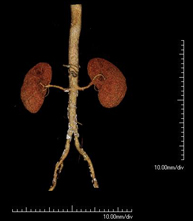

- Angio-TC aorta abdominal  Prueba diagnóstica no invasiva que consiste en el estudio de la arteria aorta abdominal obteniendo imágenes de alta definición anatómica mediante el empleo de un equipo de TC (Tomografía Computarizada) y de contraste yodado. La calidad de las imágenes permite realizar reconstrucciones en 2D y 3D gracias a estaciones de trabajo especializadas en el estudio arterial. Está indicado en aquellos pacientes con enfermedad vascular (aterosclerosis), en aneurismas de aorta, en pacientes con dolor abdominal de posible origen vascular, en estudios pre-quirúrgicos de lesiones adyacentes a la aorta abdominal como "mapa" vascular, etc. La información obtenida de forma no invasiva es indispensable para los pacientes que requieren tratamiento percutáneo o quirúrgico. En aquellos pacientes que solo requieren un seguimiento de las lesiones vasculares, esta técnica es la técnica no invasiva de elección junto con la angio-RM. Prueba diagnóstica no invasiva que consiste en el estudio de la arteria aorta abdominal obteniendo imágenes de alta definición anatómica mediante el empleo de un equipo de TC (Tomografía Computarizada) y de contraste yodado. La calidad de las imágenes permite realizar reconstrucciones en 2D y 3D gracias a estaciones de trabajo especializadas en el estudio arterial. Está indicado en aquellos pacientes con enfermedad vascular (aterosclerosis), en aneurismas de aorta, en pacientes con dolor abdominal de posible origen vascular, en estudios pre-quirúrgicos de lesiones adyacentes a la aorta abdominal como "mapa" vascular, etc. La información obtenida de forma no invasiva es indispensable para los pacientes que requieren tratamiento percutáneo o quirúrgico. En aquellos pacientes que solo requieren un seguimiento de las lesiones vasculares, esta técnica es la técnica no invasiva de elección junto con la angio-RM.

- Angio-TC arterias renales  Prueba diagnóstica no invasiva que consiste en el estudio de las arterias renales obteniendo imágenes de alta definición anatómica mediante el empleo de un equipo de TC (Tomografía Computarizada) y de contraste yodado. La calidad de las imágenes permite realizar reconstrucciones en 2D y 3D gracias a estaciones de trabajo especializadas en el estudio arterial. Esta prueba está indicada, por ejemplo, en aquellos pacientes que sufren de HTA refractaria al tratamiento, en pacientes con lesiones renales para tener un mapa "vascular" pre-quirúrgico, etc. Prueba diagnóstica no invasiva que consiste en el estudio de las arterias renales obteniendo imágenes de alta definición anatómica mediante el empleo de un equipo de TC (Tomografía Computarizada) y de contraste yodado. La calidad de las imágenes permite realizar reconstrucciones en 2D y 3D gracias a estaciones de trabajo especializadas en el estudio arterial. Esta prueba está indicada, por ejemplo, en aquellos pacientes que sufren de HTA refractaria al tratamiento, en pacientes con lesiones renales para tener un mapa "vascular" pre-quirúrgico, etc.

- Angio-TC aorto-ilíaco Prueba diagnóstica no invasiva que consiste en el estudio de las arterias ilíacas y la aorta abdominal obteniendo imágenes de alta definición anatómica mediante el empleo de un equipo de TC (Tomografía Computarizada) y de contraste yodado. La calidad de las imágenes permite realizar reconstrucciones en 2D y 3D gracias a estaciones de trabajo especializadas en el estudio arterial. Esta prueba está especialmente indicada como estudio pre-quirúrgico (mapa vascular) antes de intervenciones percutáneas o quirúrgicas de aorta abdominal, como el estudio complementario en pacientes con isquemia de miembros inferiores, etc. Prueba diagnóstica no invasiva que consiste en el estudio de las arterias ilíacas y la aorta abdominal obteniendo imágenes de alta definición anatómica mediante el empleo de un equipo de TC (Tomografía Computarizada) y de contraste yodado. La calidad de las imágenes permite realizar reconstrucciones en 2D y 3D gracias a estaciones de trabajo especializadas en el estudio arterial. Esta prueba está especialmente indicada como estudio pre-quirúrgico (mapa vascular) antes de intervenciones percutáneas o quirúrgicas de aorta abdominal, como el estudio complementario en pacientes con isquemia de miembros inferiores, etc.